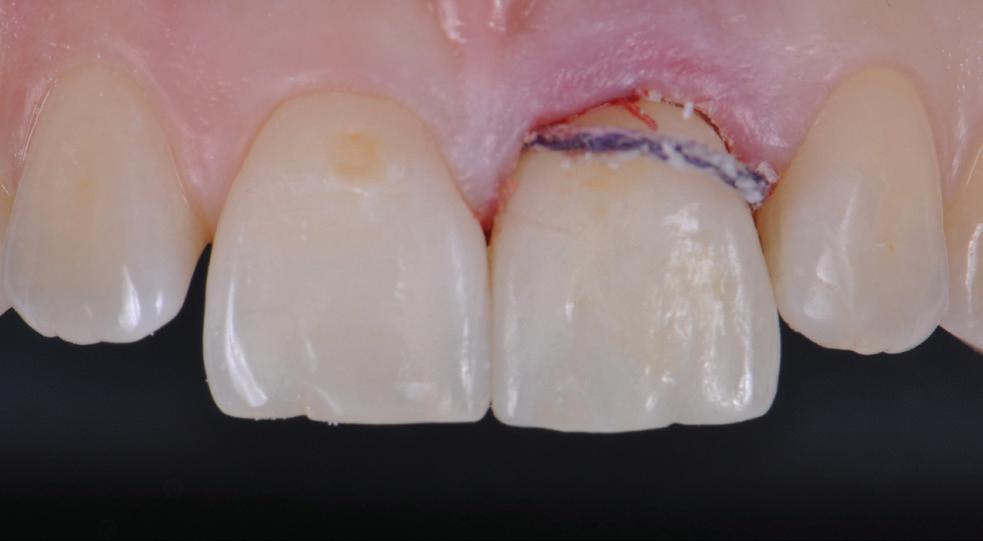

ABSORBABLE SUTURES

MONOFAST

SYNTHETIC MONOFILAMENT SUTURES MADE FROM A COPOLYMER OF POLYGLYCOLIC ACID AND POLYCAPROLACTONE (PGCL).

NON-ABSORBABLE SUTURES

PROFIMED PTFE

SYNTHETIC MONOFILAMENT SUTURES MADE FROM POLYTETRAFLUOROETHYLENE (PTFE) POLYMER.

For more details please contact our friendly customer service on 1800 776 326 or your local Distributed by Trusted by Surgeons Worldwide

surgical sutures